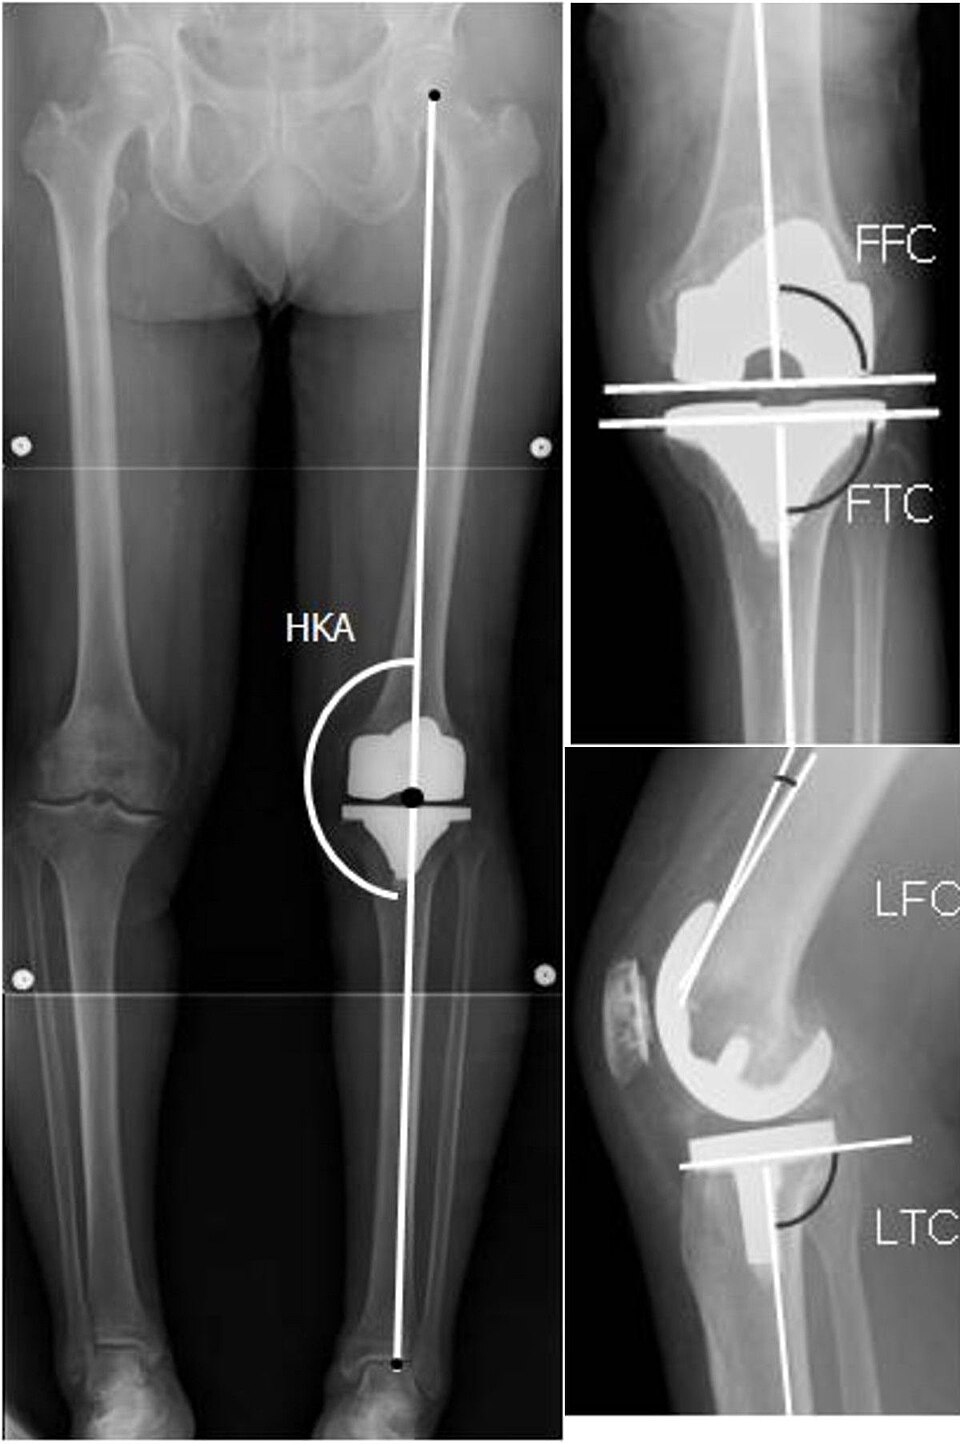

Degenerative knee with joint space narrowing, osteophytes, subchondral sclerosis, cartilage thinning, and Baker's cyst